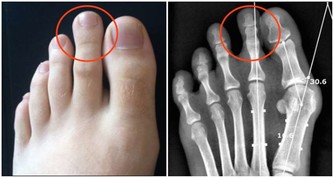

1、嗜睡貪睡 2、大便溏瀉 3、舌苔厚膩 4、腹部肥胖 5、怠惰嗜卧 6、下肢沉重 7、脘腹脹滿 8、精力下降 9、情緒抑鬱10、痰多而粘。